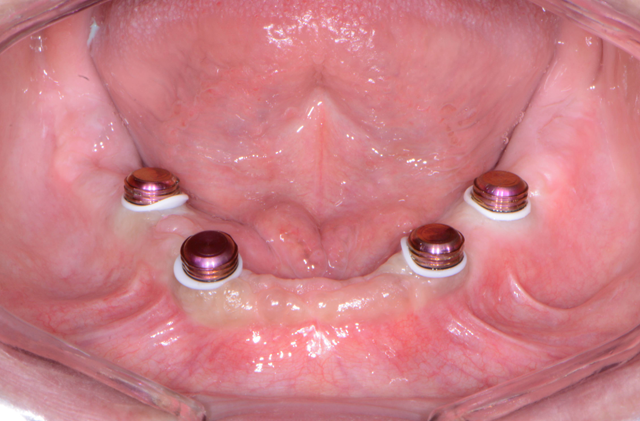

Approximately three to four months later (Fig. 12), the healing caps were removed from the Engage (OCO Biomedical) dental implants in the mandibular ridge and LOCATOR R-Tx (Zest Anchors) overdenture attachments placed (Fig. 13) and tightened to 30 Ncm. Free-standing attachments like the LOCATOR R-Tx used to retain overdentures provide numerous advantages, including enhanced esthetics and phonetics as well as ease of maintenance and simplified hygiene.

Fig. 13 Fig. 14